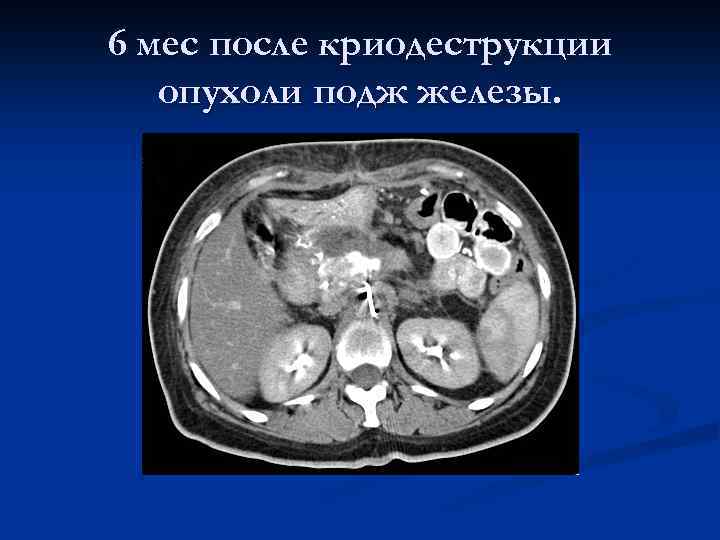

6 мес после криодеструкции опухоли подж железы.

6 мес после криодеструкции опухоли подж железы.